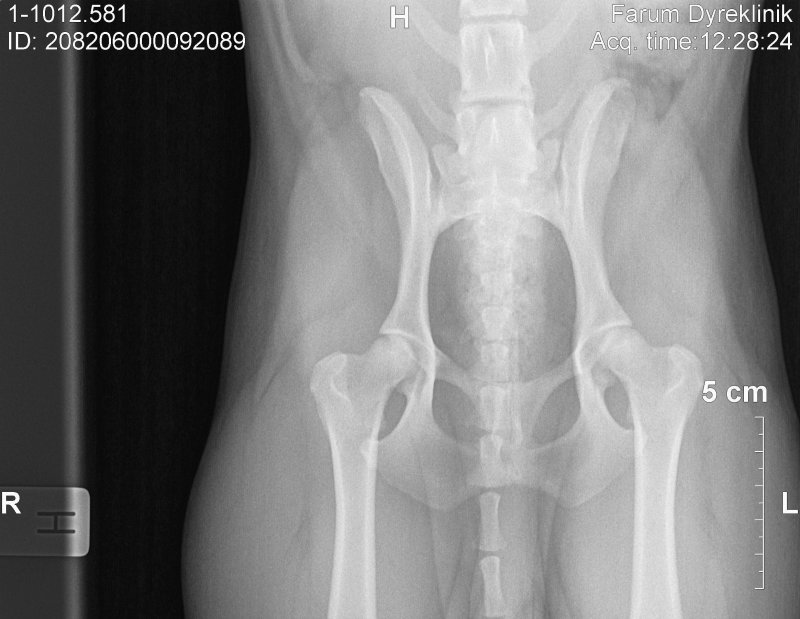

Jeff er født 12/3 2008, og er vores yngste hanhund. Han er venlig, sød og kærlig og kysser (slikker) alt og alle på sin vej. Han retter sig - stort set - ind efter Jacks og Kios anvisninger, men er også god til at få sin vilje, han er ret vedholdende. Han er altid med på en god løbeleg - han løber afsindigt stærkt og hopper utroligt højt (se her). Han er tit i hundesvømmehal, og han ELSKER det. Og så tog han næsten Kio til sig, da hun var lille, som var han hendes mor. Jeff er avlsgodkendt med karakteren XXX+. Han er 37 cm, har HD status C (B/C), og har deltaget i DKKs unghundementalltest (se nedenfor).